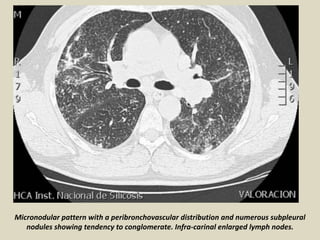

Micronodular pattern with a peribronchovascular distribution and numerous subpleural

nodules showing tendency to conglomerate. Infra-carinal enlarged lymph nodes.